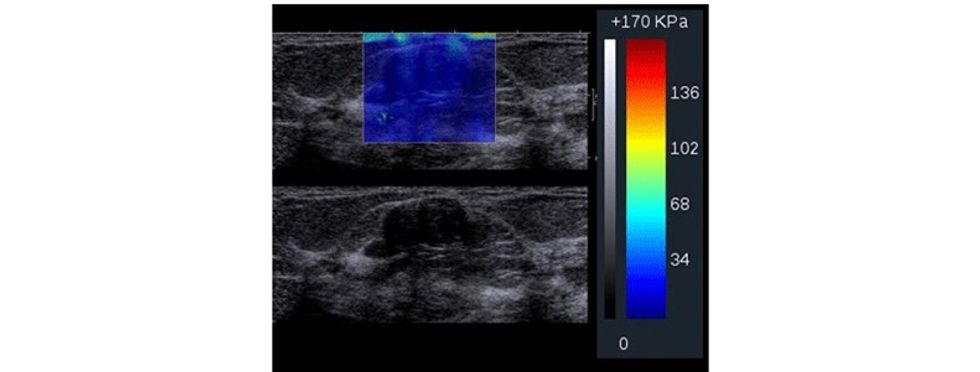

Të dhënat e fituara përpunohen përmes paketës softuerike në formë të color mapping apo grayscale për të vizualizuar zonën me interes e cila ekzaminohet.

Parimet bazë te elastografisë bazohen në dukurinë që indet nën kompresion shfaqin tendosje dhe kjo do të paraqitet me karakteristika të ndryshme. Prandaj, nën kompresion, në boshtin aksial, duke bërë matjet, mund të vlerësohet ngurtësia dhe elasticiteti i indit, para dhe pas kompresionit, ndërsa imazhi i paraqitur dhe i llogaritur quhet elastogram, ku fushat me ngurtësi të rritur dhe elasticitet të ulur paraqiten me ngjyrë të kaltër.

Me aplikimin e elastografisë krahas ultrazërit konvencional, mundësohet që të rritet specificiteti i ultrazërit, sidomos në lezionet e kategorizuara me BiRads 4, duke bërë përcaktimin e elasticitetit të indit, detektim të qartë të nivelit të elasticitetit të indit dhe, marrë parasysh që formacionet me natyrë malinje kanë dendësi më të lartë dhe elasticitet të ulur gjatë aplikimit të kompresionit në boshtin aksial e shprehur në kPa. Pastaj me anë të mapingut qartë detektohet natyra e lezionit.